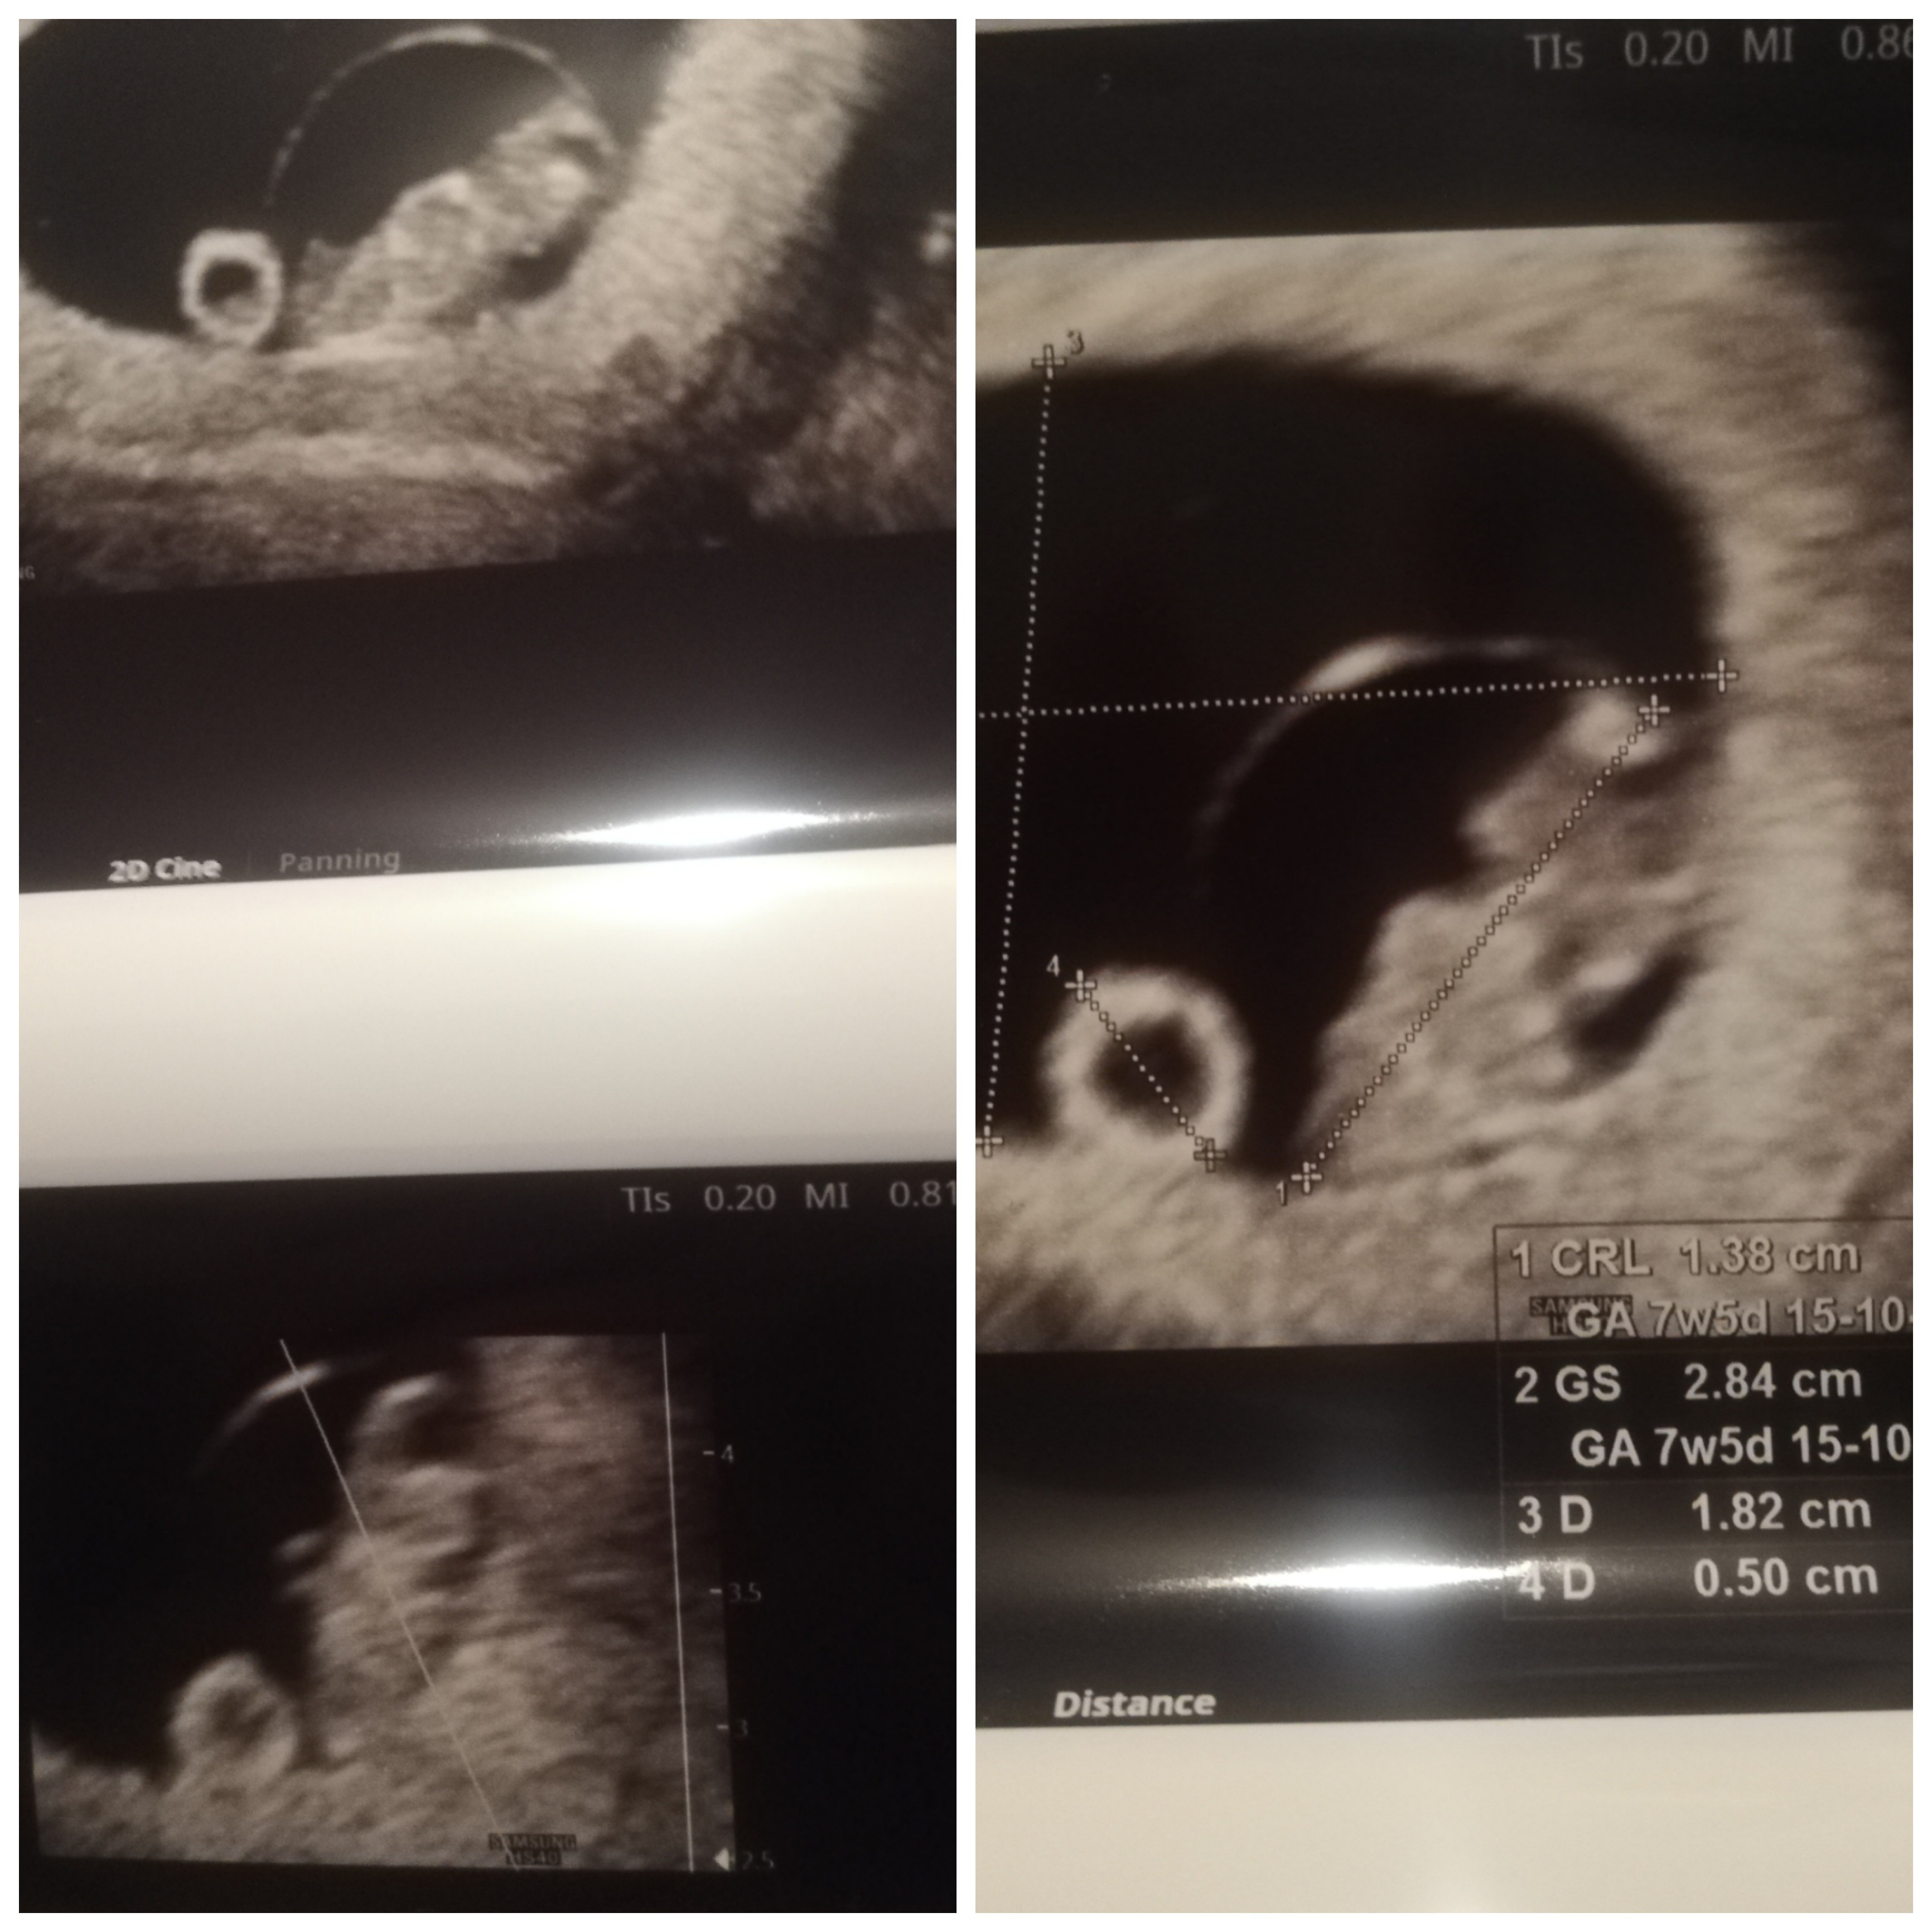

Wróciłam! 😁 Moje Smoczysko jest o tydzień starsze niż wynikało by z om. Ma 1.38 cm i serce jak dzwon. Gin był wielce zdziwiony, że dwa tygodnie temu inny lekarz nie zobaczył nawet pęcherzyka.

30 marca mam już prenatalne. Gin namówił mnie na testy pappa. Dodatkowo, ze względu na podwyższoną glukozę dostałam glukometr w gratisie z nakazem kontrolowania się codziennie 🙂

Jest pięknie! 😍 Jestem taka spokojna i szczęśliwa, że wszystko jest dobrze. Myślałam, że nie skończę się mojemu ginowi podlizywać 😅

• PicsArt_03-03-10.13.14.jpg

PicsArt_03-03-10.13.14.jpg

981,9 KB · Wyświetleń: 94